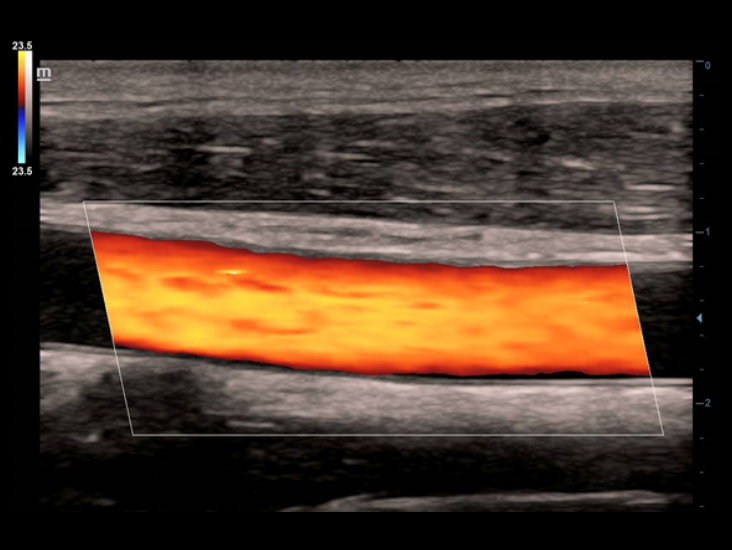

ComboWave

ComboWave - ―ç―²–Ψ ―É–Ϋ–Η–Κ–Α–Μ―¨–Ϋ–Α―è ―²–Β―Ö–Ϋ–Ψ–Μ–Ψ–≥–Η―è –¥–Μ―è –Μ–Η–Ϋ–Β–Ι–Ϋ―΄―Ö –¥–Α―²―΅–Η–Κ–Ψ–≤. –ë–Μ–Α–≥–Ψ–¥–Α―Ä―è –Ω―Ä–Η–Φ–Β–Ϋ–Β–Ϋ–Η―é –Ϋ–Ψ–≤–Ψ–≥–Ψ ―²–Η–Ω–Α –Κ–Ψ–Φ–Ω–Ψ–Ζ–Η―²–Ϋ–Ψ–≥–Ψ –Ω―¨–Β–Ζ–Ψ―ç–Μ–Β–Κ―²―Ä–Η―΅–Β―¹–Κ–Ψ–≥–Ψ –Φ–Α―²–Β―Ä–Η–Α–Μ–Α –¥–Α―²―΅–Η–Κ–Η DC-40 ―¹ Full HD –Η–Φ–Β―é―² –±–Ψ–Μ–Β–Β –≤―΄―¹–Ψ–Κ―É―é –Ω―Ä–Ψ–Η–Ζ–≤–Ψ–¥–Η―²–Β–Μ―¨–Ϋ–Ψ―¹―²―¨ –±–Μ–Α–≥–Ψ–¥–Α―Ä―è ―Ä–Α―¹―à–Η―Ä–Β–Ϋ–Ϋ–Ψ–Φ―É –Α–Κ―É―¹―²–Η―΅–Β―¹–Κ–Ψ–Φ―É ―¹–Ω–Β–Κ―²―Ä―É –Η –±–Ψ–Μ–Β–Β –Ϋ–Η–Ζ–Κ–Ψ–Φ―É –Α–Κ―É―¹―²–Η―΅–Β―¹–Κ–Ψ–Φ―É –Η–Φ–Ω–Β–¥–Α–Ϋ―¹―É.